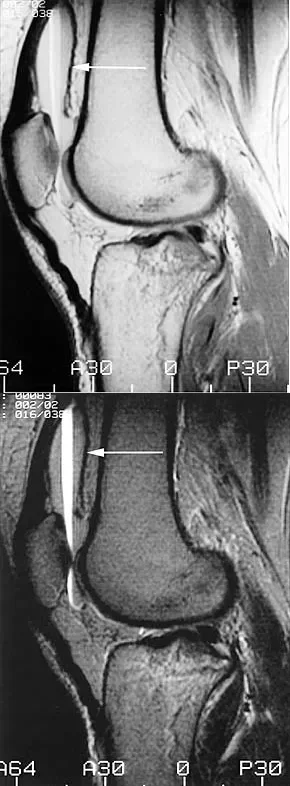

The MRI scans shown demonstrate a lipohemarthrosis in the knee. Which of the following is the most common underlying etiology for this specific MRI finding?

Explanation

Correct Answer: C

Lipohemarthrosis is characterized by the layering of fat and blood within a joint cavity. The most common cause is an intra-articular fracture, which allows marrow fat to escape into the joint space. On MRI, it typically shows a superior layer of fat, a central layer of serum, and an inferior layer of red blood cells. While an ACL tear causes a hemarthrosis, it does not typically cause a lipohemarthrosis unless accompanied by an osteochondral fracture.

A patient presents to the emergency department with acute knee swelling following a high-energy trauma. T1-weighted MRI is obtained and shown. The distinct layering effect seen in the suprapatellar pouch is most strongly associated with which of the following underlying injuries?

Correct Answer: Intra-articular fracture

The MRI scan demonstrates a lipohemarthrosis, characterized by the layering of fat, serum, and red blood cells in the joint space. The superior layer contains fat (high signal intensity on T1), the middle layer contains serum, and the dependent layer contains red blood cells. The presence of a lipohemarthrosis is highly indicative of an intra-articular fracture, which allows marrow fat to escape into the joint cavity. While ligamentous and meniscal injuries can cause a hemarthrosis, they do not typically introduce marrow fat into the joint unless accompanied by an osteochondral defect or fracture.

A patient presents with acute knee swelling following trauma. MRI scans (T1 and T2-weighted) are shown. The layering effect seen within the joint space is most strongly associated with which of the following underlying injuries?

The MRI shows lipohemarthrosis, characterized by layering of fat (superior, high signal on T1), serum (central, low signal), and red blood cells (inferior, low signal). This finding is highly indicative of an intra-articular fracture, which allows marrow fat to escape into the joint space.